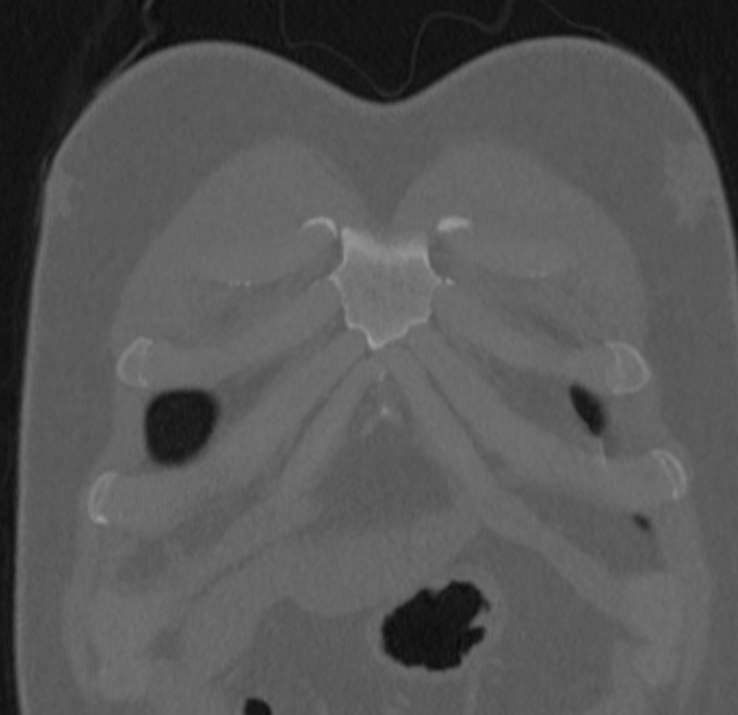

Мультиспиральная компьютерная томография ребер проводится в рамках протокола КТ органов грудной клетки. Грудина, ребра, грудной отдел позвоночника составляют костный каркас грудной клетки и при проведении КТ оценивается наличие деструктивных изменений в этих костных структурах.

КТ ребер является быстрым безболезненным высокоточным методом обследования костных структур грудной клетки. Метод позволяет получить детальные снимки и трехмерные цифровые изображения костно-мышечного каркаса грудной клетки. КТ широко используется в хирургии и травматологии при планировании оперативного вмешательства и в дальнейшем помогает оценить результаты проведенной операции.

Компьютерная томография ребер позволяет обнаружить:

- дегенеративно-дистрофические изменения ребер, суставов

- воспалительные процессы как в ребрах, суставах, так и в прилегающих тканях и органах.

- травмы ребер, суставов

- осложнения после операции.

- новообразования

- метастазы

- планирование операций.